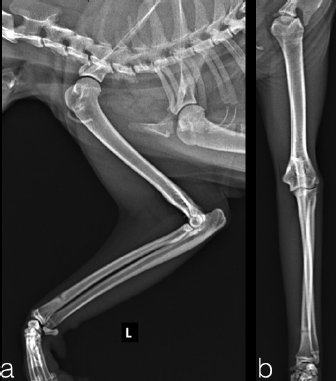

Two, spayed, Domestic Shorthaired cats with an age of 1.5 years (case 1) and 6 years (case 2) were referred to the author’s clinic for the non-weight bearing left forelimb lameness after a suspected trauma. Physical examination, of both cats, revealed moderately swollen and painful left elbow, with abnormal posture characterized by extended rotation of antebrachium and supination of the paw. Orthogonal radiographs of forelimbs demonstrated a complete caudal elbow luxation (Fig. 1). The radius and ulna were caudally and proximally displaced in relation to the humerus; furthermore, in case 1, a small avulsion bone fragment (2 mm diameter) closed to the lateral aspect of the humeral condyle was presented. No other abnormality was identified during the physical and radiographic examinations. The cats were sedated by intramuscular administration of dexmedetomidine (Dexdomitor: Pfizer Italia Srl, Rome, Italy) (10 μg/kg) and methadone (Semfortan: Dechra Veterinary Products Srl, Turin Italy) (0.4 mg/kg). General anesthesia was induced with propofol (Proposure: Merial Italia Spa, Milan, Italy) (6 mg/kg) intravenously and, after oro-tracheal intubation, maintained with isoflurane (IsoFlo: Aesica Queenborough Limited, Kent, United Kingdom) and oxygen. Modified closed reduction technique was attempted in both cases. Distal traction of antebrachium with full extension of the elbow was initially achieved followed by simultaneously applying distal pressure on the olecranon and partial elbow flexion. Following successful reduction, the collateral ligaments integrity was indirectly assessed with the Campbell’s test (1971), with normal limits value around 110° of supination and 70° of pronation recorded in both patients. The joint stability and reduction were maintained with gentle manipulation. However, instability was present at 100° of elbow extension, while major stability was obtained at 40° of flexion. For this reason, the elbow was held at 40° of flexion and a simple transarticular external skeletal fixator type IIa was applied to maintain the stability of the joint. Due to the forced flexion position, which limited the biomechanics movement, the cats were not able to weight bearing in the postoperative period. Two full pins, smooth Kirschner wires 2.0 mm of diameterf were inserted in the proximal third of the diaphysis of the humerus and in the distal third of the radial diaphysis. Stainless steel connecting bars (Gènia. St. Hilaire de Chaléons, France) (3.0 mm) were positioned medially and laterally connecting with Maynard clamps (Gènia. St. Hilaire de Chaléons, France) to the full pins (Fig. 2). The avulsion bone fragment was not treated in case 1. The patients were discharged from the clinic 24 hours after surgery. Cage rest without any exercise was recommended for 2 weeks and meloxicam (Meloxoral: Fatro S.p.A., Ozzano Emilia, Italy) (0.05 mg/kg) was administrated for 7 days.

Fig. 2. Transarticular external skeletal fixator type IIa applied to maintain the stability of the joint (case 1).